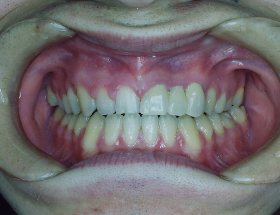

主訴:歯の凸凹を治したい。被せも白色を希望。診断名:上下叢生。年齢36歳。前歯は透明,奥歯は金属製のエッジワイズ装置にて治療。歯は抜いていませんが、少し削って細くしています。治療期間1年。治療費:矯正料670000円 調整料 2000円~5000円が約12回。リスクと副作用:歯を抜かずに並べているので後戻りの対策として裏からの固定が必要です。歯茎も腫れやすい性質なので、定期検診が重要となります。